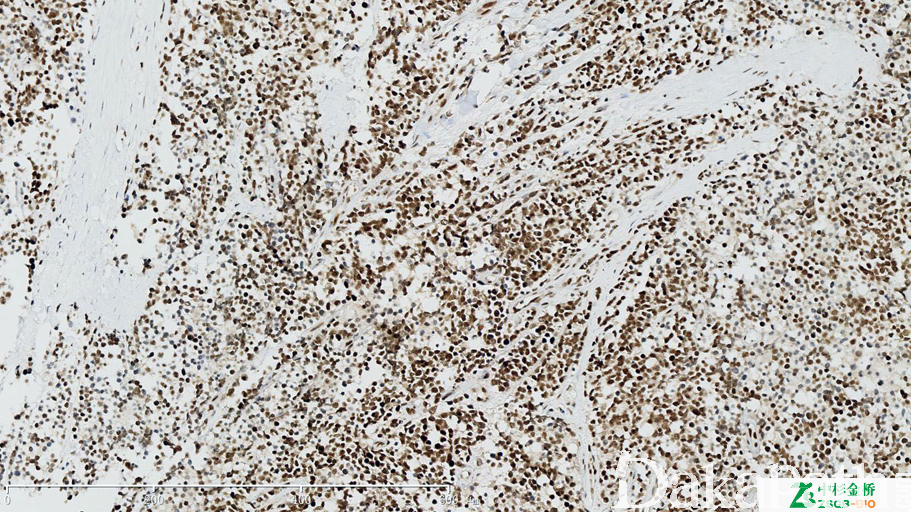

FLI-1

参与细胞增生、肿瘤发生及血管形成。>10%细胞核阳性为阳性判断的标准

信号定位: 胞核

在肿瘤中的表达情况:

几乎全部阳性(≥95%的病例阳性): 血管内膜肉瘤、血管内皮细胞瘤,Kaposi 型、上皮样血管内皮瘤、Burkitt 淋巴瘤、血管瘤、上皮样血管瘤、卵巢卵泡膜细胞瘤、血管肉瘤、梭形细胞血管瘤、前列腺高级别上皮内瘤变

通常阳性(<95%,≥75%的病例阳性): 血管内皮瘤,NOS、毛细血管瘤、尤文肉瘤、Kaposi 肉瘤、上皮样血管肉瘤、卵巢硬化性间质瘤、上皮样肉瘤

经常阳性(<75%,≥55%的病例阳性): 血管周细胞瘤、胰腺实性假乳头状肿瘤、原始神经外胚层瘤、促结缔组织增生性小圆细胞肿瘤、T 细胞淋巴瘤、乳腺浸润性癌,非特殊类型